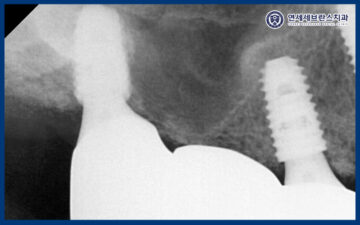

오른쪽 위 첫 번째 큰 어금니 부위는

앞서 말씀드린 것처럼

잇몸뼈의 양이 충분하지 않은 상태였기 때문에,

상악동 측방 거상술을 통해

부족한 뼈를 보강한 후

임플란트를 식립하였습니다.

상악동거상술을 통해

임플란트가 안정적으로

자리 잡을 수 있는 충분한 공간을 확보하고,

장기적인 예후를 고려한

치료를 진행하였습니다.